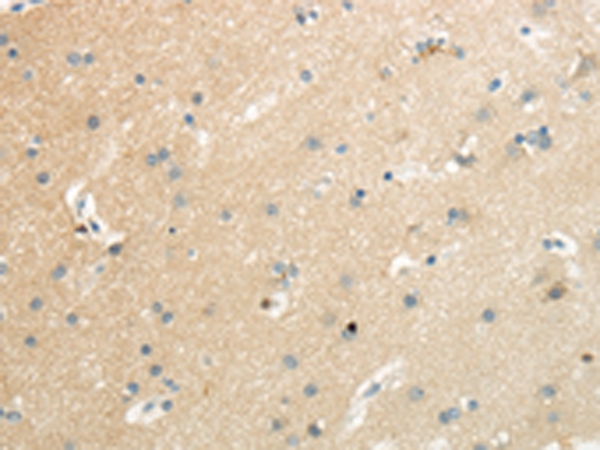

Immunohistochemical analysis of paraffin-embedded Human brain tissue using #43437 at dilution 1/35.